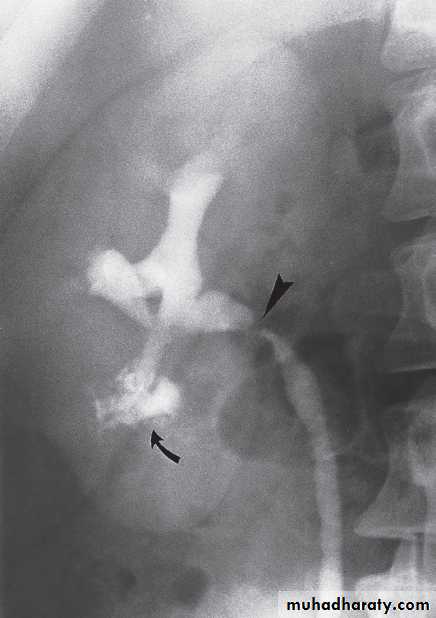

-Congenital intrinsic pelviureteric junction obstruction(PUJ obstruction ):The diagnosis depends on identifying dilatation of the renal pelvis and calices, with an abrupt change in calibre at the PUJ with normal ureter .

• The earliest change on the post contrast films is irregularity of a calix. Later, a definite contrast-filled cavity maybe seen adjacent to the calyx.

• Strictures of any portion of the pelvicaliceal system or ureter may occur, producing dilatation of one or more calices.

The multiplicity of strictures is an important diagnostic feature.